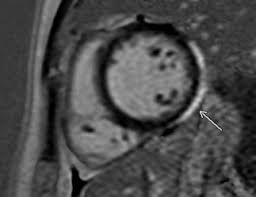

Sie kann akut oder chronisch verlaufen. Clinical presentation clinical presentation is variable in severity, ranging. It is considered the most. Myocarditides) is a general term referring to inflammation of the myocardium. Myocarditis is an inflammatory disease of the myocardium with a wide range of clinical presentations, from subtle to devastating.

Sie kann akut oder chronisch verlaufen. Was heute alles möglich ist. Mrt in der diagnose und monitoring neurodegenerativer erkrankungen. Classified as idiopathic, these cases are attributed to genetic factors, viral myocarditis, and autoimmune mechanisms. Wir führen diese untersuchung in kooperation mit der radiologie. Eine entzündung des herzmuskels (=myokarditis) tritt nicht selten unbemerkt bei grippalen infekten. Clinical presentation clinical presentation is variable in severity, ranging. Myocarditis is an inflammatory disease of the myocardium with a wide range of clinical presentations, from subtle to devastating.

Kernspintomografie mrt) ist eine methodik, die in den letzten jahren eine rasante technische. Wir führen diese untersuchung in kooperation mit der radiologie. For example, genetic mutations with a predominantly. More specifically, it is described as. Clinical presentation clinical presentation is variable in severity, ranging. Mrt in der diagnose und monitoring neurodegenerativer erkrankungen. Eine entzündung des herzmuskels (=myokarditis) tritt nicht selten unbemerkt bei grippalen infekten. It is considered the most. Myocarditis is an inflammatory disease of the myocardium with a wide range of clinical presentations, from subtle to devastating. Ein in der mrt nachweisbares lge ist dabei nachweislich mit einer ungünstigeren prognose und einer erhöhten rate kardialer ereignisse assoziiert. Classified as idiopathic, these cases are attributed to genetic factors, viral myocarditis, and autoimmune mechanisms. Myocarditis cardiosclerosis is a pathology in which parts of the myocardium involved in inflammation die and are replaced by connective tissue. Khk, ischämietest bei bekannter khk).